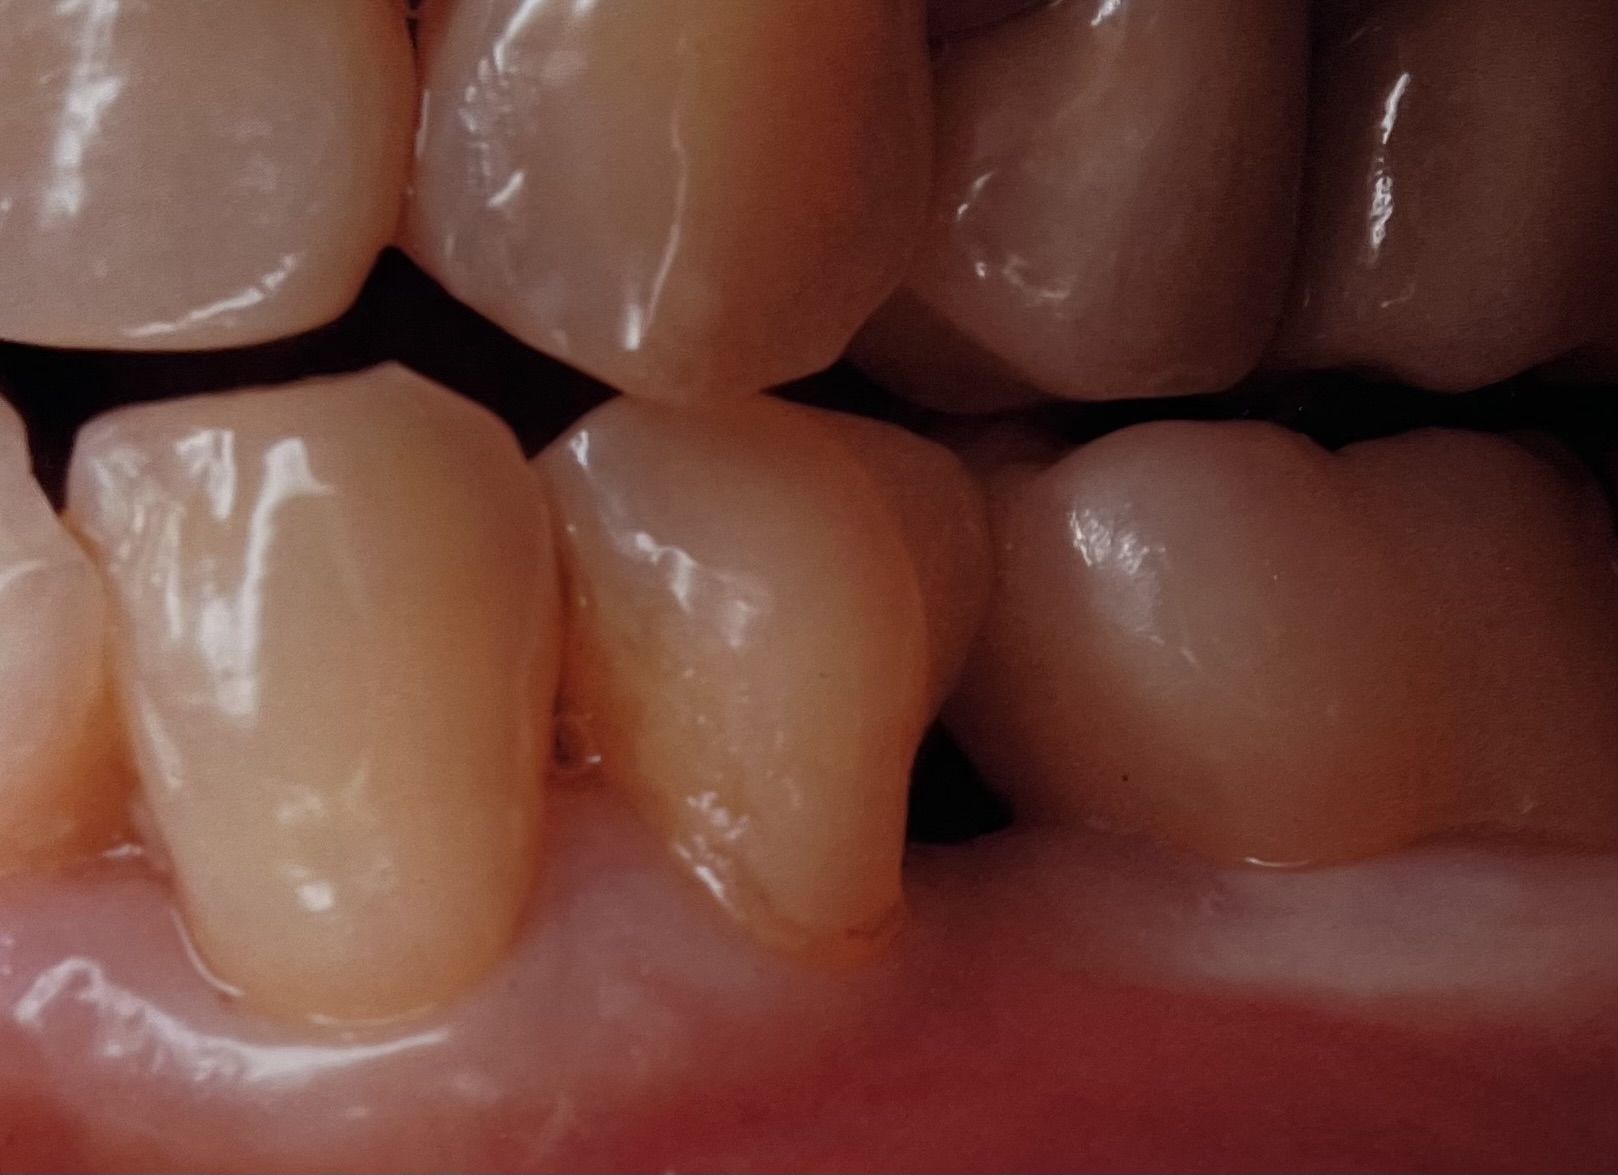

上が術後、下が術前です、治療前スペースが大きな物が溜まりやすい状態でした、また写真で見えない歯茎の下まで虫歯が進んでプラスチックで治療してありました、

そこで上の虫歯と一緒に冠タイプとし、冠の歯茎からの立ち上がりで歯茎を押すというテクニックを使いました、そうすると歯茎との相性のよいジルコニアセラミックの場合、歯肉を押すことで少し歯肉の位置が上がってくれます、

そして、歯の形を院内で(CADデザインで)作れることを利用して、できるだけ、隣の歯とのスペースが少なくなるように調整をして作製しました、

その結果、物が詰まりにくく、隣の歯のスペースと近似した歯茎のスペースを作り出すことに成功しました、

また、歯茎のスペースはプラスチックだった物がセラミックになったことにより段違いにプラークがつきにくくなっています(ジルコニアセラミックは赤染をしても赤くならないくらいプラークがつきにくく滑沢で長持ちします)